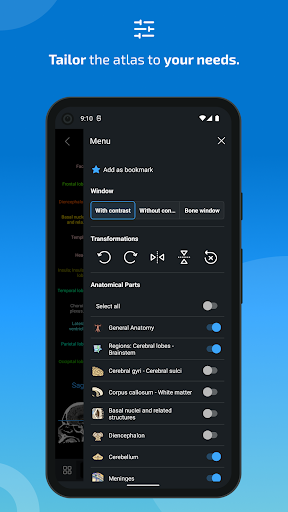

-Added dark mode.

- The anatomic view now displays more labels

- You can now hide structures one by one (new button inside the description popup) and display them again in the right menu